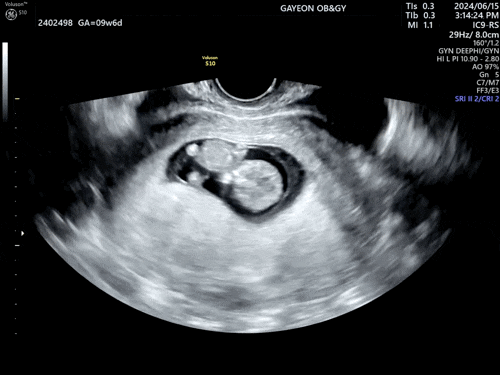

[임신10주] 두 번째 산부인과 검진.

24년 6월 15일. 정기 검진을 위해 방문한 산부인과. 산전검사 보건소에서 받을 거면 검사받고 결과지 꼭 챙...